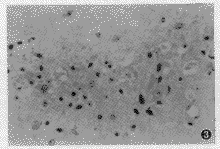

表1结果显示,在SE 30 min内,CA1和CA3区神经元即 有丢失,但与对照组比较无显著性差异,此时已有N-乙酰天门冬氨酸(NAA)值减低;SE 3 h后,光学显微镜下观察CA1和CA3 区几乎没有正常神经元,为变性、坏死神经细胞或由胶质细胞充填(图3)。MRS检测发现胆碱(Cho)升高和γ-氨基丁酸(GABA)降低;大鼠SE 0.5 h内 乳酸(Lac)值无变化,SE 3 h乳酸升高,至 60 h仍保持高水平状态。经等级相关统计学检验,NAA值与癫痫持续时间呈显著负相关(γs=-0.78,P<0.01),与海马CA1区和CA3区正常神经元数量呈显著正相关(γs=0.79,P<0.01),即发作时间越长,NAA值越低,海马区正常神经元数量越少,NAA值越低。

表2结果显示,对照组无阳性病理发现,SE 30 min即有海马神经元变性,少许坏死,SE 3 h后可见较严重的神经元坏死,胶质增生(即海马硬化),细胞浆和间质水肿,而且随癫痫持续时间延长而加重(图3)。

图3 癫痫持续18 h,大鼠海马CA3区可见大量神经元坏死、溶解、脱失,胶质细胞增生明显,形成“海马硬化”(HE ×400)